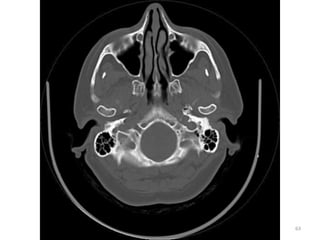

1. Medula espinal

(forame magnum)

2. Células mastóideas.

3. Seio maxilar esq.

4. Côndilo

mandibular(cabeça).

5. Processos zigomáticos.

6. Maxilar.

7. Osso nasal.

31